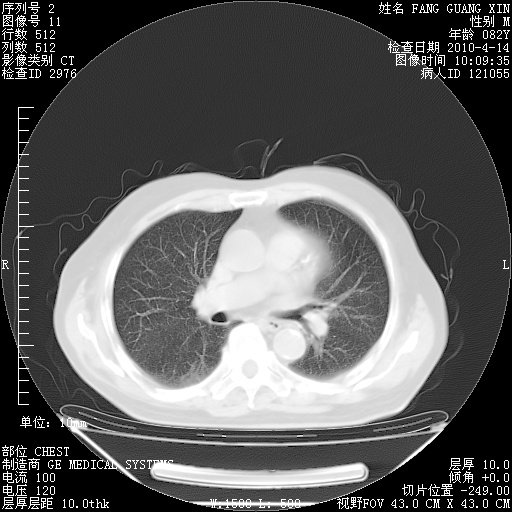

肺部CT平扫未见异常。